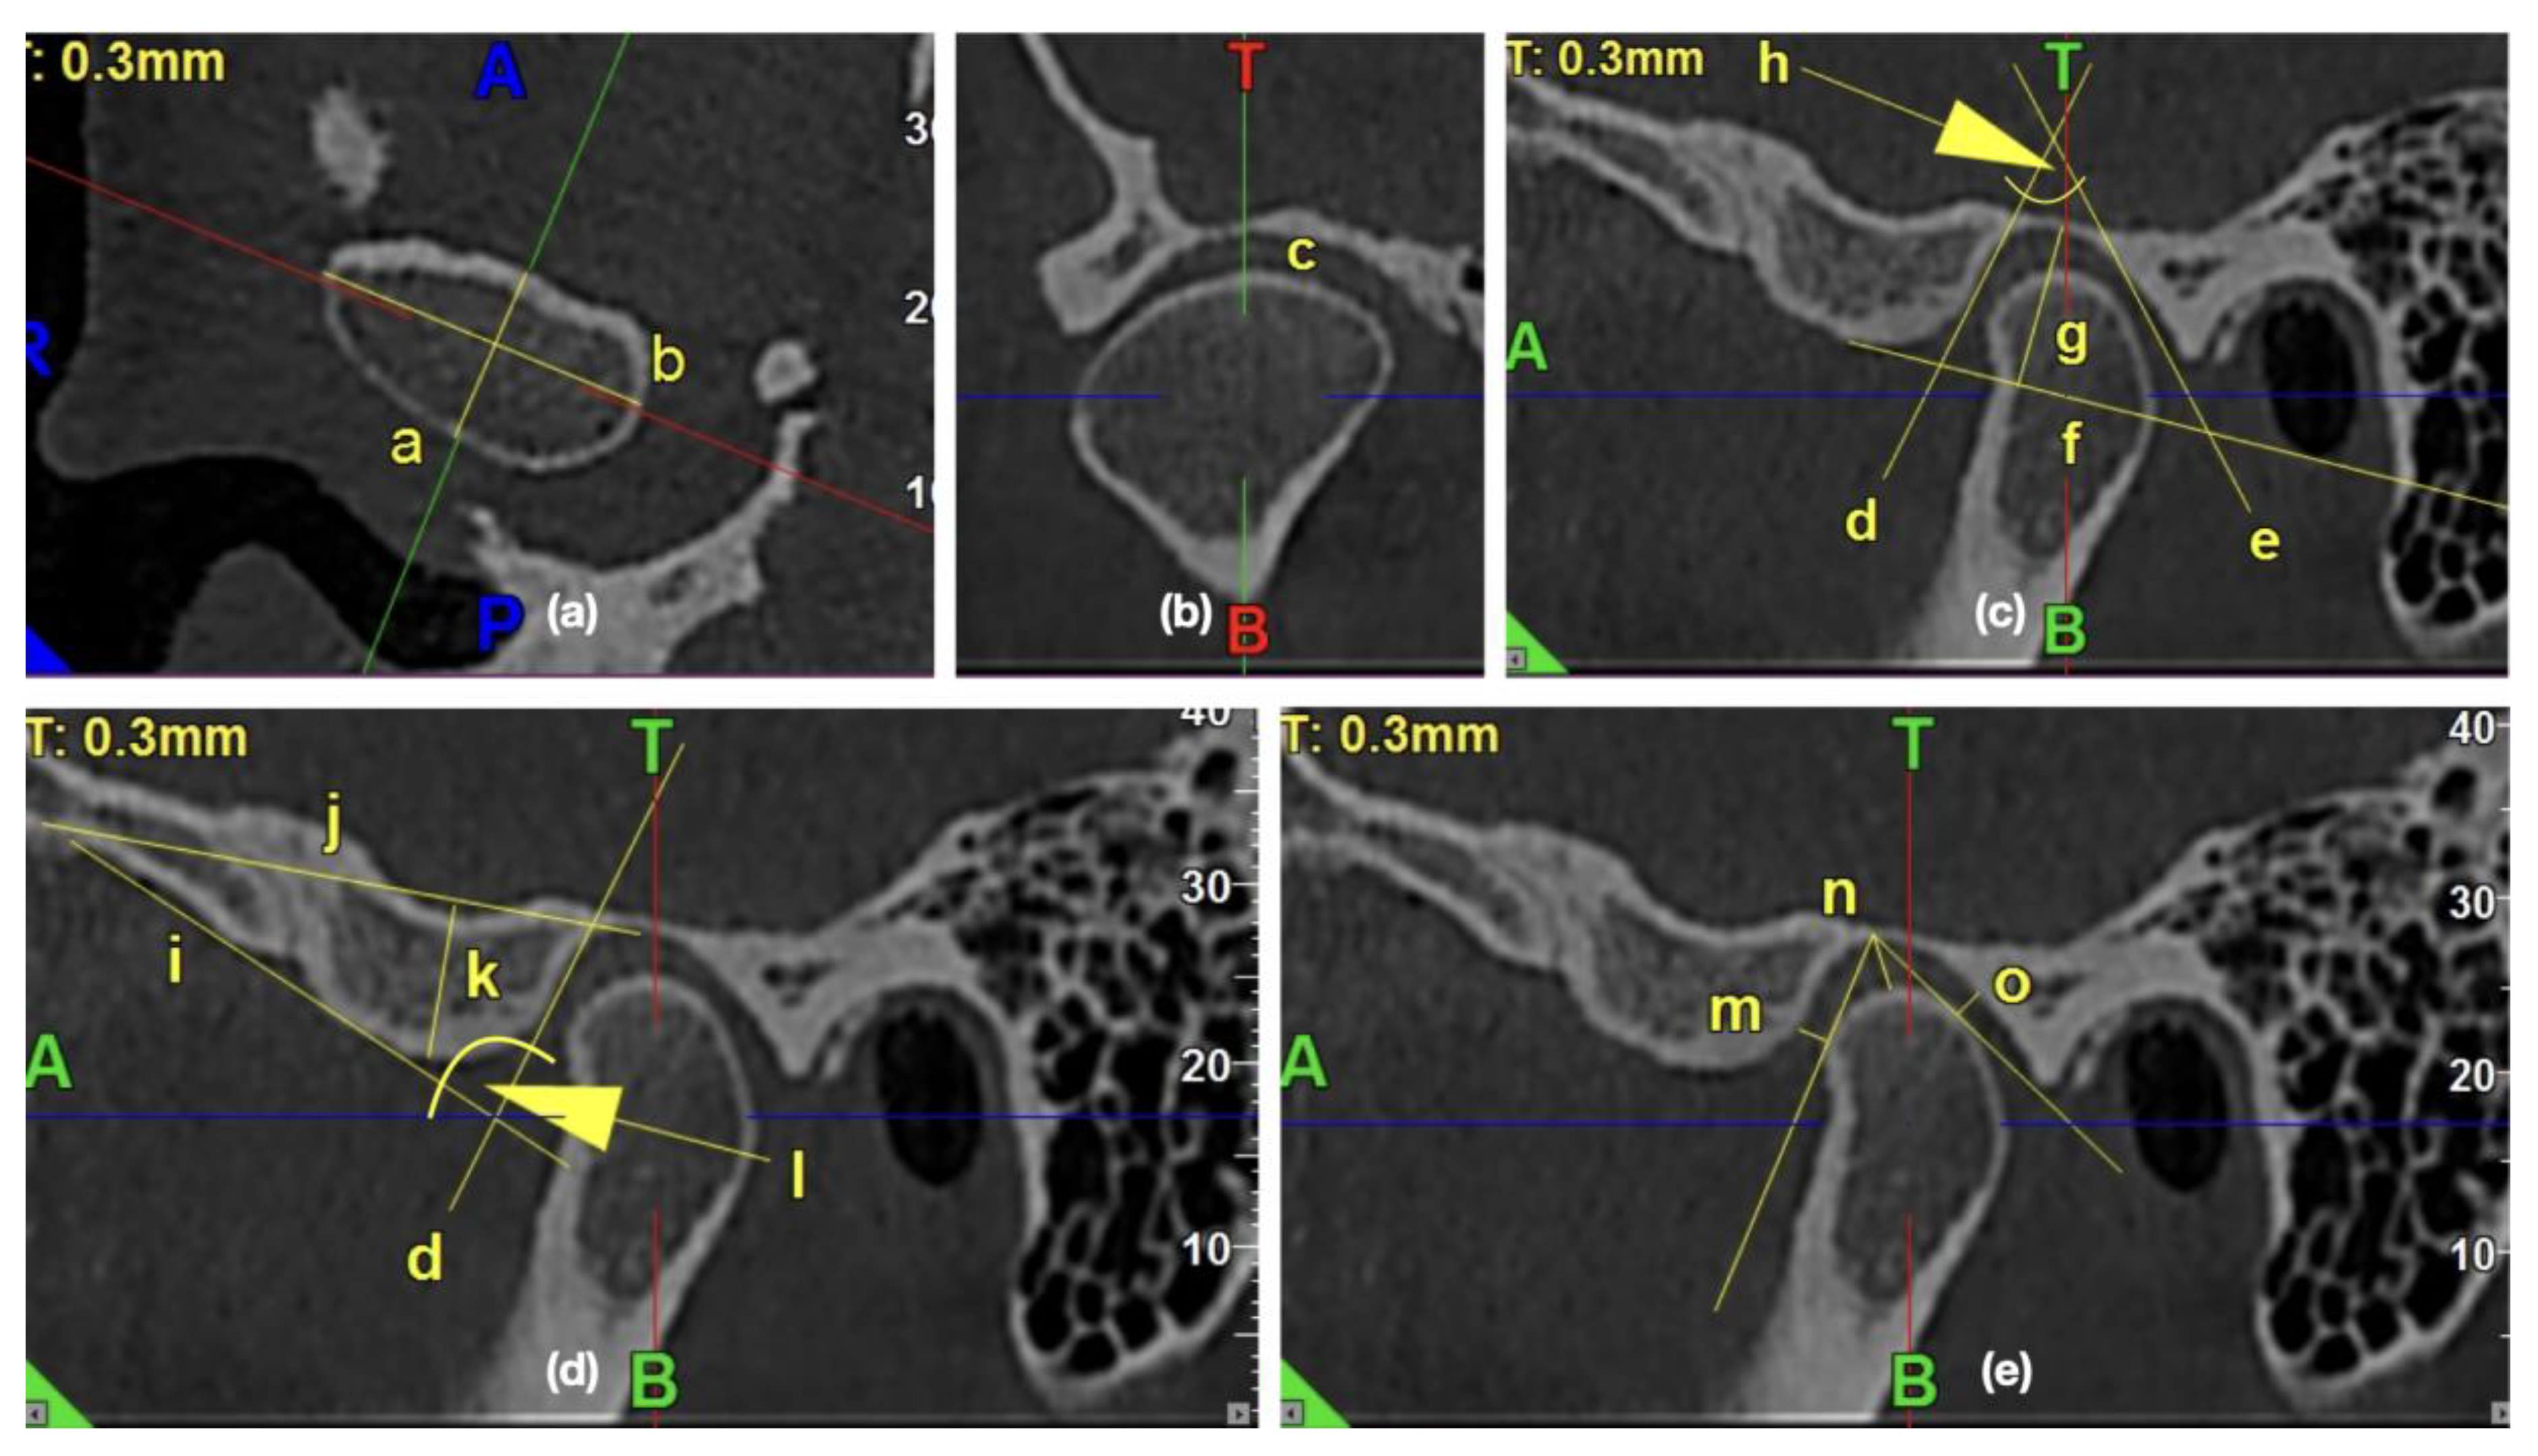

All the measurements were performed with the use of iRYS Softwarwe version 6.2. The primary outcome was the assessment of the impact of the osteoarthritic changes on the temporomandibular joint’s morphology. The 0.3-mm thickness axial slice of the condyle, in which the condyle had the maximum mediolateral dimension, was selected for further measurements. The sagittal axis was established as a line, which was perpendicular to and, at the same time, crossing the middle of the line connecting the mesial and distal end of the condyle. The obtained sagittal and coronal images were further examined and measured. Figure 2 presents the exemplary lines, points, and angles in the TMJ CBCT scans used for measurements.

Figure 2.

The exemplary lines, points, and angles in the temporomandibular joints (TMJ) cone beam computed tomography (CBCT) scans used for measurements. (a) Morphology of mandibular condyle in the axial view: /a/condylar A-P dimension, /b/condylar width; (b) Shape of condyle head in the coronal view: /c/condyle’s superior surface view assessment; (c) Morphology of glenoid fossa in the sagittal view: /d/PE line, /e/AT line, /f/glenoid fossa basal line, /g/glenoid fossa depth, /h/glenoid fossa divergence angle; (d) Morphology of articular eminence in the sagittal view: /i/AE line, /j/eminence basal line, /k/articular eminence height, /l/articular eminence divergence angle; (e) Assessment of anterior, posterior, and superior joint spaces in the sagittal view: /m/anterior joint space, /n/superior joint space, /o/posterior joint space.